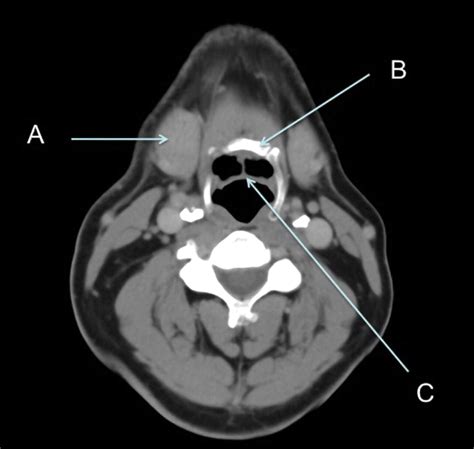

A CT scan of neck, often referred to as computed tomography, is a sophisticated diagnostic imaging procedure that utilizes X-rays combined with computer processing to create detailed, cross-sectional images of the structures within your neck. Whether your physician is investigating a persistent lump, evaluating unexplained pain, or monitoring a known condition, this imaging tool provides a level of clarity that standard X-rays cannot match. By capturing slices of the neck’s anatomy—including the thyroid gland, lymph nodes, blood vessels, and spinal structures—doctors can pinpoint abnormalities with remarkable precision, making it an essential component in modern diagnostic medicine.

The technology behind a CT scan of neck is fascinating. The patient lies on a motorized table that slides into a large, doughnut-shaped scanner. As you move through the scanner, an X-ray tube rotates around you, sending thin beams of radiation through your body. Detectors on the opposite side of the scanner record these beams, and the computer processes this information to create detailed, 3D-like images of the internal structures.